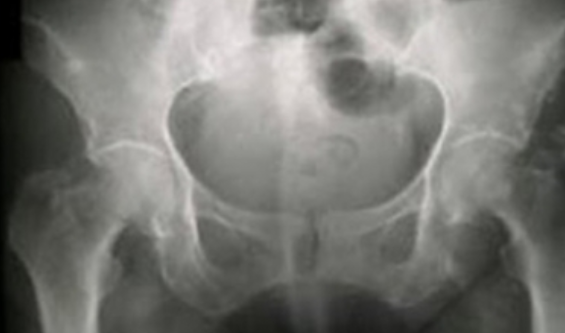

Aunque son diversas las causas este tipo de dolor, normalmente se piensa que su origen está en el desgaste de los discos lumbares que cambian con el tiempo y se van desplazando, lo cual se conoce como hernia de disco.

En una resonancia magnética, un disco desgastado luce más oscuro, por lo que determinar si están relacionados con dolor de cadera puede ser complicado.

El proceso para determinar si los discos son la causa del dolor en la cadera empieza con la evaluación directa por parte de un profesional de la salud y un examen detallado de la espalda, pues en la espalda lumbar, los glúteos y la región de la cadera, hay varias otras estructuras que pueden provocar malestar en la cadera, pero sin que tengan relación con la edad.(NOTIMEX)]